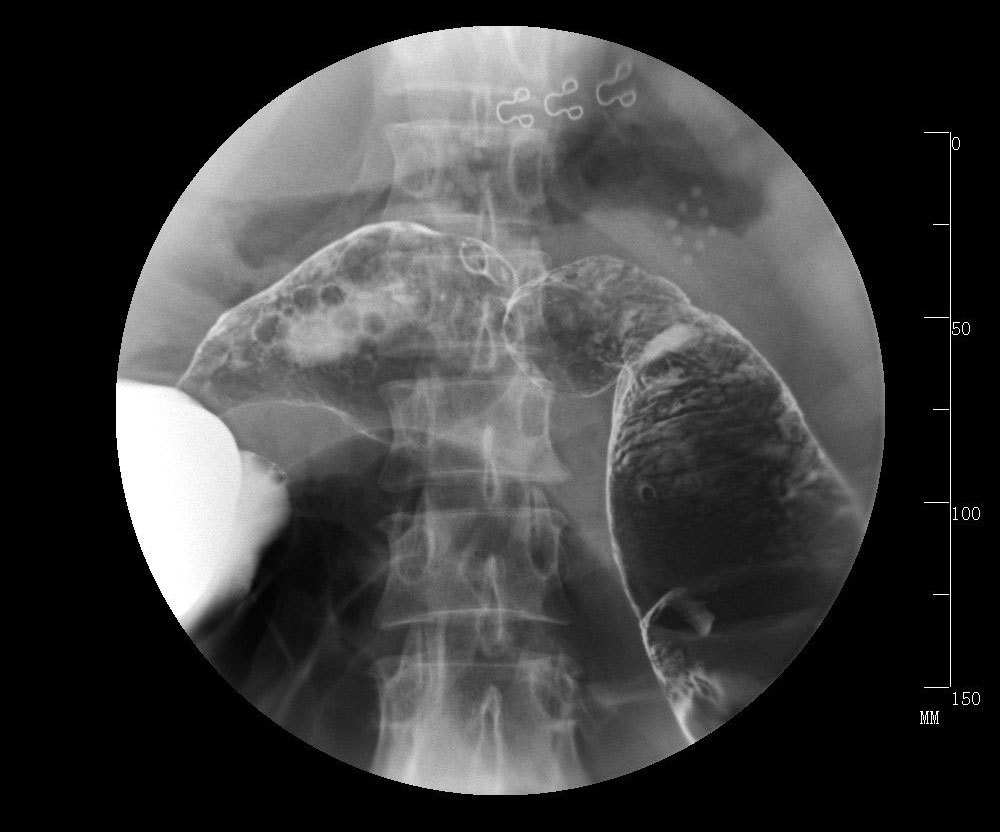

慢性結(jié)腸炎的病因及癥狀

在我們平時(shí)生活當(dāng)中大家一定聽(tīng)說(shuō)過(guò)結(jié)腸炎這種疾病,但是對(duì)于慢性結(jié)腸炎大家可能就不是很了解了,慢性結(jié)腸炎也是結(jié)腸炎的其中一種,主要是因?yàn)榻Y(jié)腸炎反復(fù)發(fā)作而引起的一種疾病,那么慢性結(jié)腸炎是怎么引起的呢,有哪些癥狀呢,下面我就給大家介紹一下這方面的內(nèi)容: